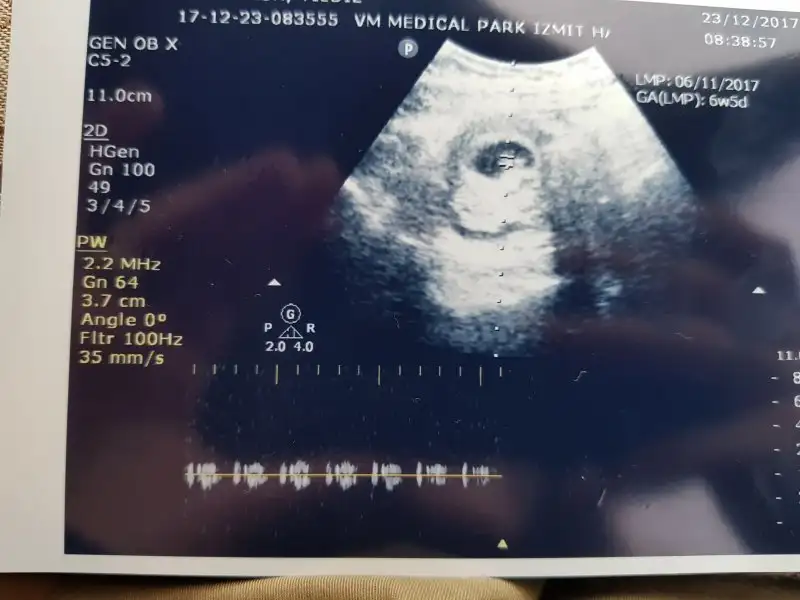

Kizlar bizimde cinsiyetimiz hakkinda yorum yapabilirmisinizz lütfen 6+5 haftalik

IMG-20171223-WA0009.webp

Resmi yakından bir daha yükleyeyim . 3 değil yani doktor öyle bir şey demedi :) ilk yüklediğim resim de öyle anlaşıldı sanırım.